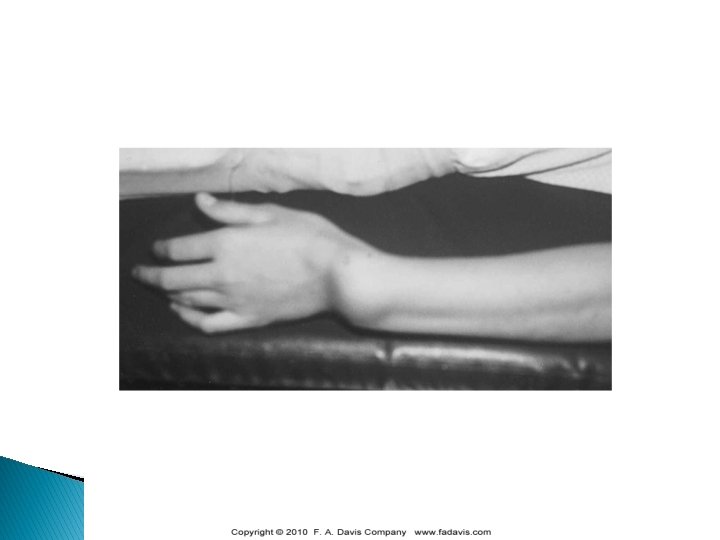

Volar Plate Injury